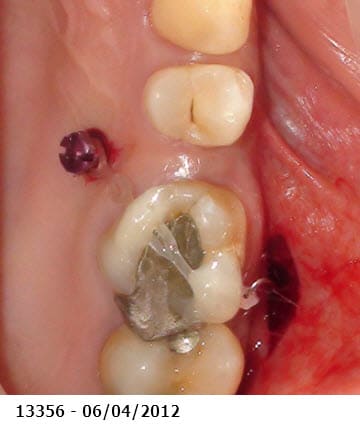

Patiente moins de 40 ans, qui a un peu laissé trainer les choses et désire s'en occuper maintenant. Elle pensait avoir droit aux complets mais je lui ai tout de suite dit "mais nooooooooon !". Possibilités financières limitées (pas d'implanto).

Les égressions dues au manque de calage postérieur sont ici extrêmes. La dévitalisation + élongation coronaire + couronnes ou bridges plus ou moins dans la courbe de Spee des molaires maxillaires, risque de me faire atteindre les furcations.

La seule solution viable est chirurgicale et implantaire car en plus les molaires sup ont déjà une grosse perte osseuse (furcation sur la 27 ? - parodontite chronique ?) donc pas de plastie osseuse possible en conservant les dents postérieures.

les papilles n'ont pas l'air au mieux de leur forme

hygiène ?

motivation ?

tabac ?